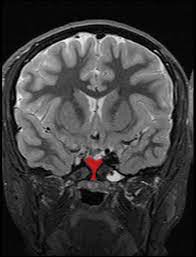

Morning Glory Sign Midbrain Radiology Reference Article Radiopaedia Org

Convolvulaceae - Morning-glory family. Graphically this is identified on an axial image at the level of the midbrain by drawing 1. These old-fashioned favorites love to climb.